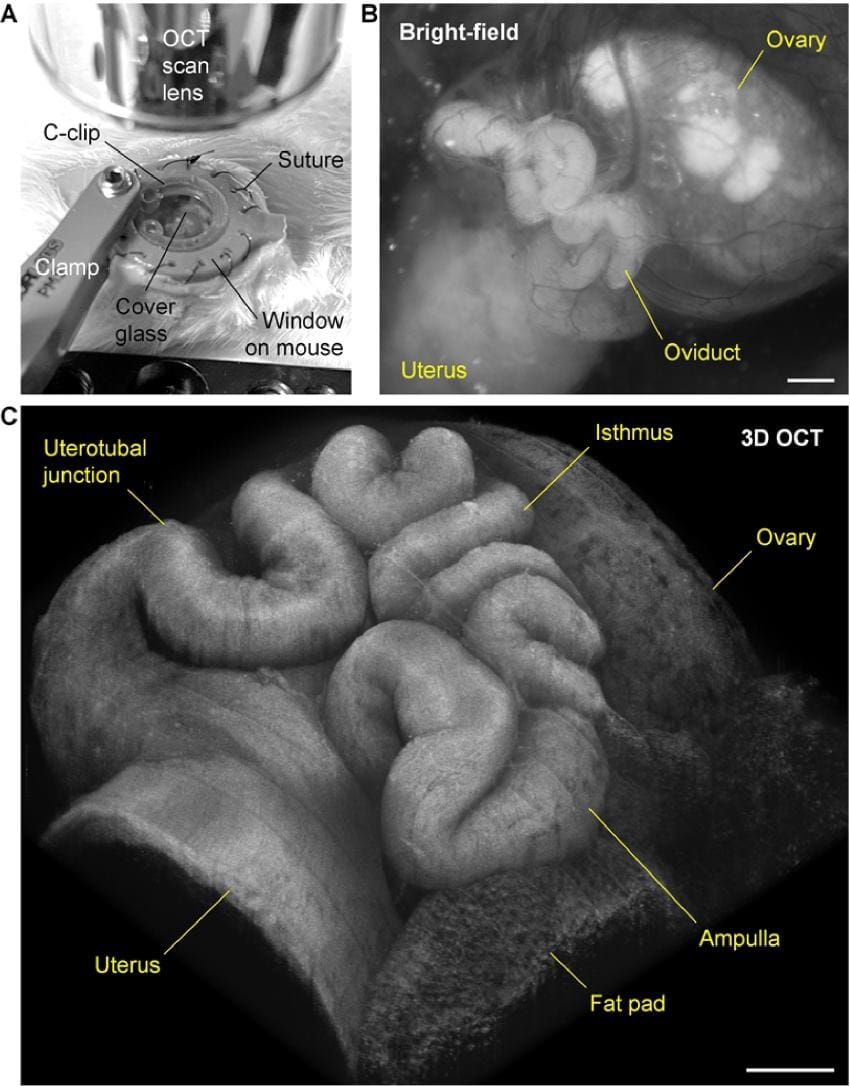

A collection of three images. The first shows a small circular window implanted into the skin of a mouse. The second shows a 2d greyscale image of an ovary, fallopian tube, and uterus. The third is a highly detailed 3d image of the organs.

(A) In vivo imaging setup with a clamp stabilising the window implanted on the right dorsal side of the mouse. (B) In vivo bright-field image of the oviduct as well as the ovary and a portion of the uterus through the window. (C) In vivo 3D OCT image of the oviduct showing its 3D morphology and structure through the window. Scale bars are 500 µm. Credit: Han et al 2025, Biomedical Optics Express, DOI:10.1364/BOE.565065